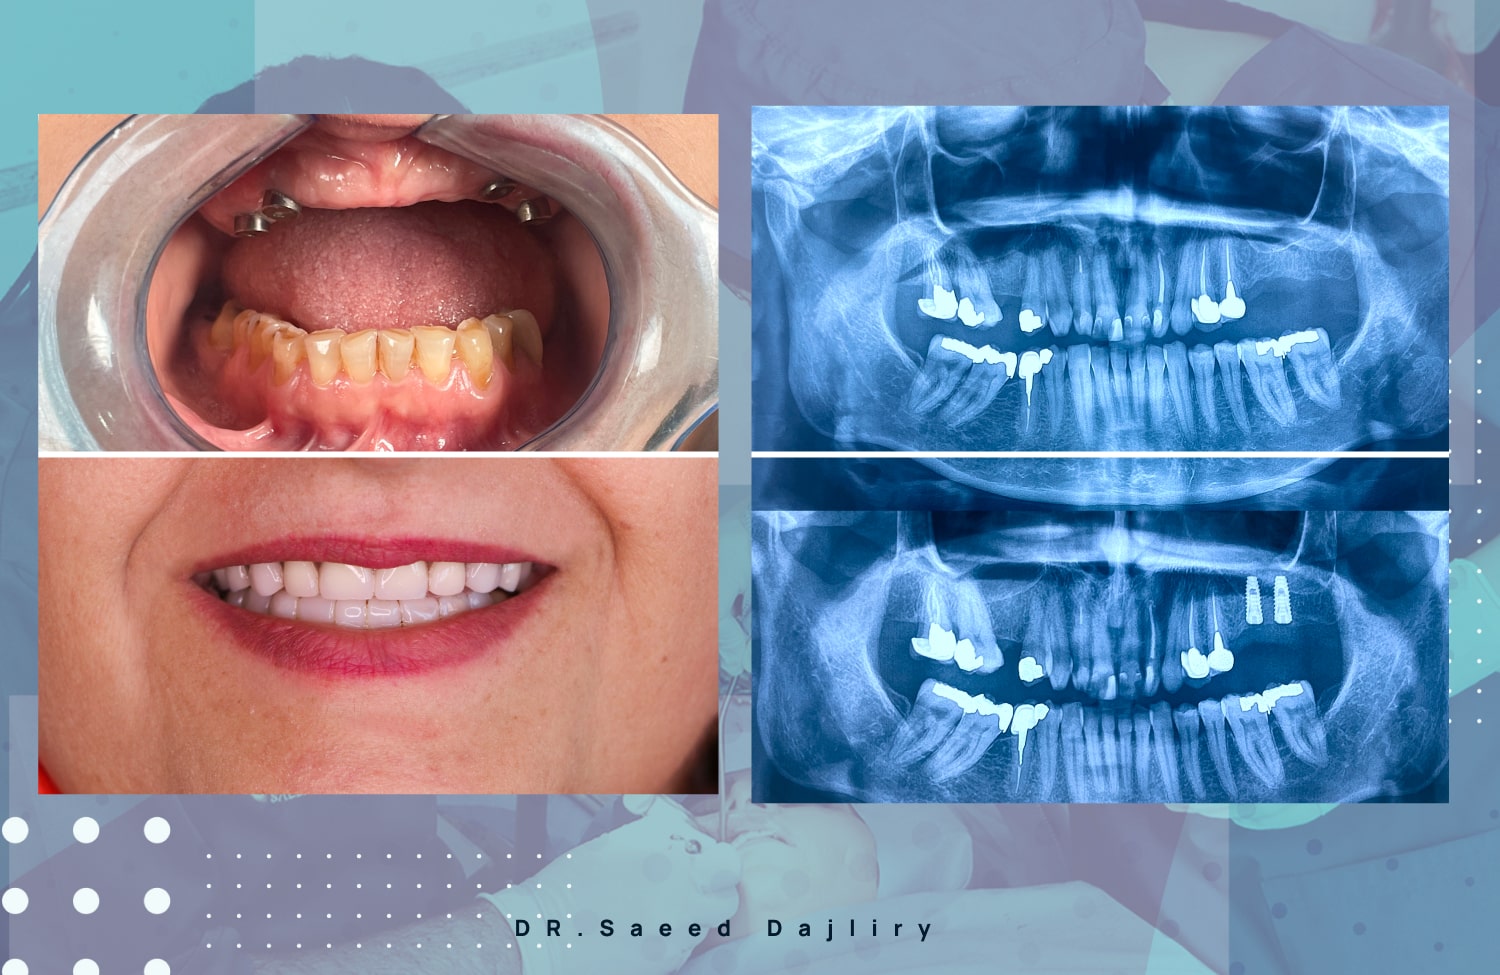

در این مقاله، دکتر سعید داج لیری – یکی از متخصصان مطرح در زمینه جراحی ایمپلنت در رشت – به بررسی تمام نکات کلیدی میپردازد. اگر شما هم به دنبال ایمپلنت بدون درد در رشت یا حتی امکان دریافت ایمپلنت قسطی در رشت هستید، خواندن این مطلب به شما کمک خواهد کرد.

انتخاب پزشک نقش بسیار مهمی در موفقیت جراحی ایمپلنت دارد. تجربه، دقت و استفاده از تجهیزات مدرن، عواملی هستند که باعث میشوند بیماران، دکتر سعید داج لیری را بهعنوان یکی از بهترین دکترهای ایمپلنت در رشت انتخاب کنند.